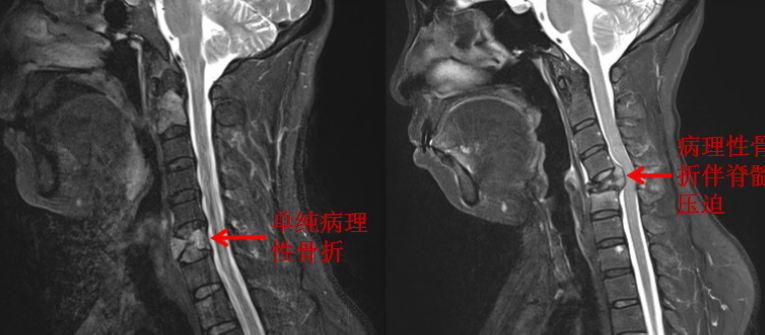

张阿姨也一样,是肺癌晚期的患者,她和戴阿姨有着同样难忍的疼痛,不过张阿姨没有那么幸运,她转移癌的位置位于高位脊柱——颈椎,而且阿姨已经有了明显的双手肌肉力量减退、麻木、疼痛等表现,且颈椎较为特殊,如果单纯注入水泥的话,肿瘤在远期可能会进一步“啃食”我们的骨头,进一步加重骨质破坏,导致脊柱不稳,而颈椎后面走形的是我们比较高位的颈髓,如果出现压迫损伤,不仅会导致肢体的疼痛、麻木、无力,甚至导致四肢瘫痪,严重者呼吸肌无力,无法呼吸,如无及时抢救,甚至死亡。所以我们在手术注入骨水泥的同时,也会通过固定的钉棒系统,进行颈椎的固定,保持颈椎稳定性。